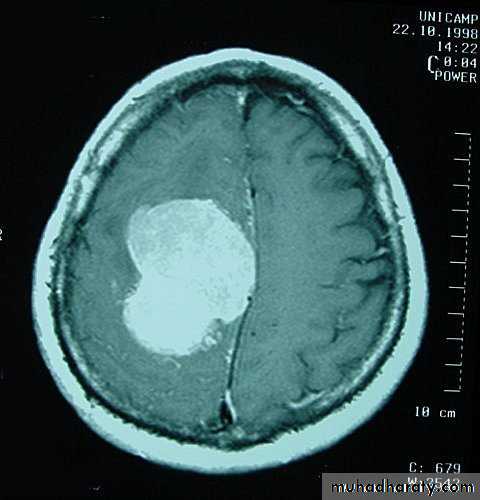

Metastatic Brain TumoursMRI

Neurosurgery